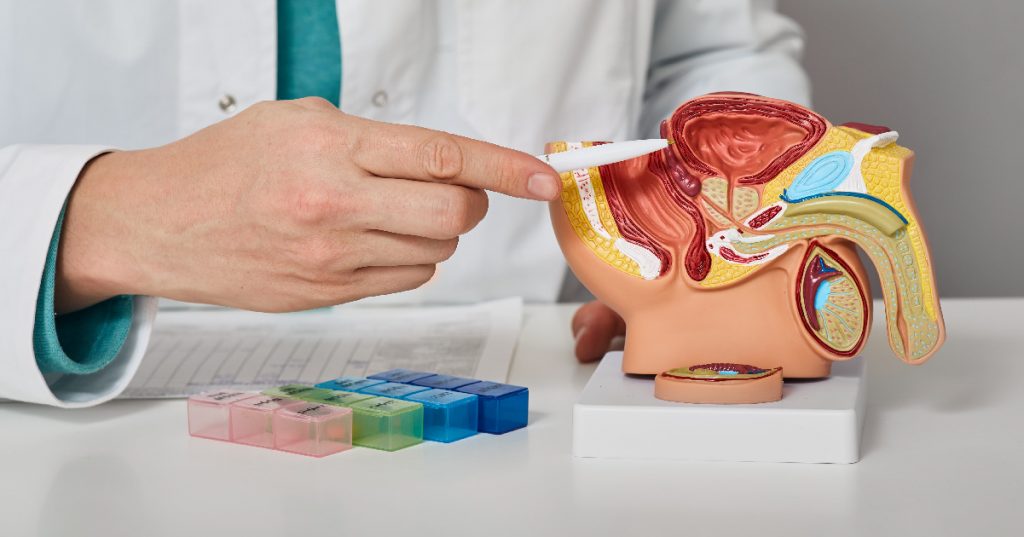

بخش اول: پروستات و وظایف آن پروستات غدهای کوچک به اندازه یک گردو است که بخشی از سیستم تناسلی مردان را تشکیل میدهد. وظیفه اصلی پروستات تولید مایعی است که بخش عمدهای از مایع منی را تشکیل میدهد. این غده در زیر مثانه و اطراف مجرای ادراری قرار دارد، و هر گونه افزایش حجم پروستات میتواند به فشرده شدن مجرای ادراری و مشکلات در دفع ادرار منجر شود.

بخش چهارم: تشخیص BPH برای تشخیص BPH، پزشک از چندین روش استفاده میکند:

1. معاینه مقعدی دیجیتال (DRE): پزشک با لمس پروستات از طریق مقعد، اندازه و شکل آن را بررسی میکند.